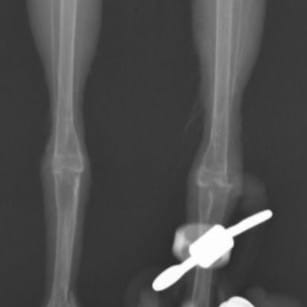

約2週間後の再診では再脱臼せず、普通に歩けていました。

レントゲン検査でも問題なくはまっています。